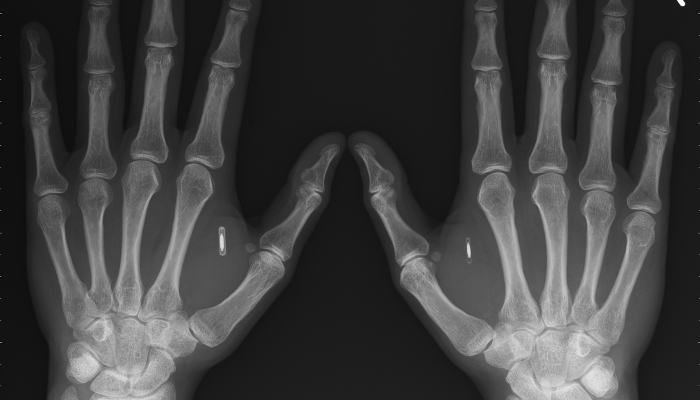

Para McCauley es cuestión de tiempo – muy poco – que todos comencemos a llevar chips implantados en nuestro cuerpo. Él mismo explica que lleva uno insertado en su mano.

En el chip que lleva en su mano tiene conectividad con su smartphone, una capacidad de 1GB de memoria, donde almacena datos sanitarios o contraseñas.

“En dos o tres años la gente que tiene enfermedades como diabetes tendrá un chip interno que medirá cosas como la glucosa en sangre, o también personas con riesgo de cardiopatía lo llevarán”, agrega McCauley.

A las funciones médicas se sumarán otras posibilidades. “Comando y control”, explica el experto. “Abrir la puerta de casa, o el coche, o hacer una búsqueda en internet” será posible desde estos chips insertados en nuestro cuerpo.